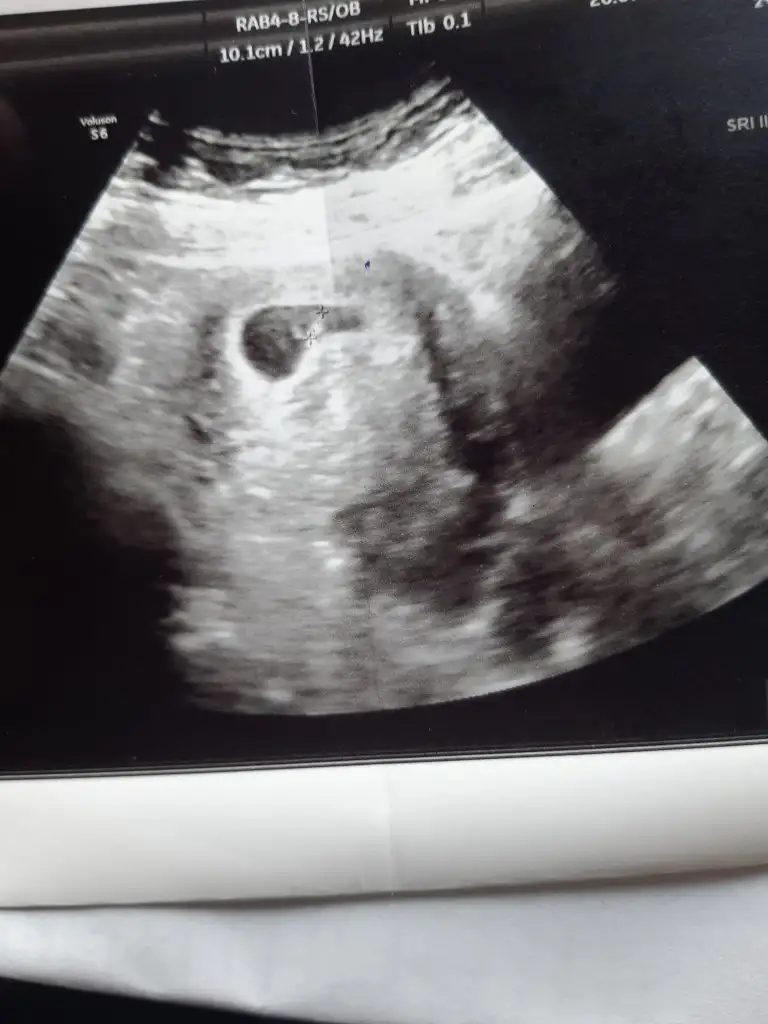

Kızlar 17sinde yumurtlamam oldu. Yani 10.günü bugün. 1 haftadır göğüs ucu ağrısı çekiyorum. Dünde göğüslerim taş gibi oldu. Ve gece rüyamda testimi pozitif gördüm. Uyanır uyanmaz yaptım. Sizde görüyor musunuz? Daha tahminen adetime 4 yada 5 gün var